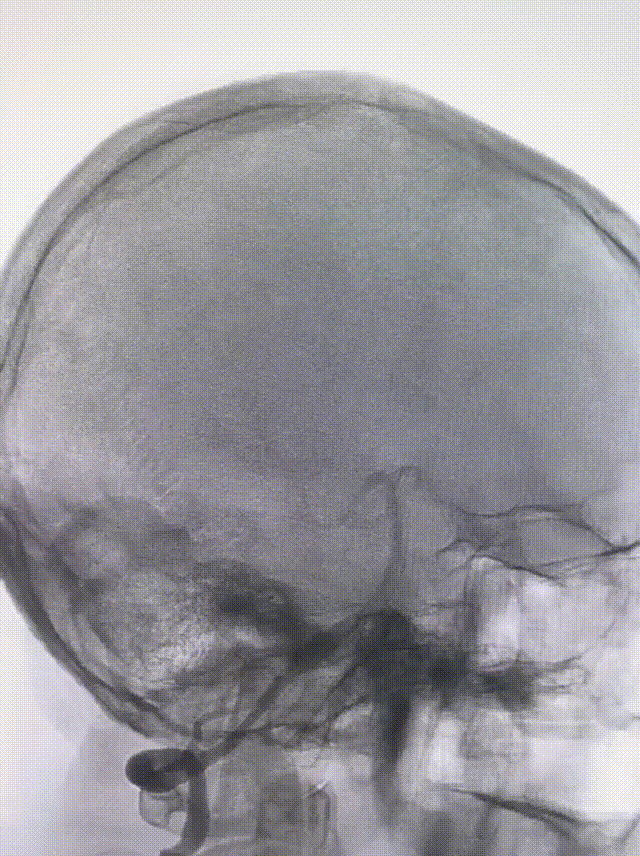

经桡动脉穿刺,132cm Simmons导管带7F 105 EasyRadial™输送导管过弓成攀超选右侧椎动脉。

132cm Simmons导管送至V2段末端输送导管。

微导丝带XT-27微导管至基底动脉尖。

将EasyRadial™输送导管送至V3段保持支撑。

造影测量血管直径3.5,选择4.0*30mm 密网支架释放。

密网支架释放完毕造影,显示支架打开良好。

将EasyRadial™输送导管撤至近端V2段动脉瘤处,释放7.0*40mm 血管支架。

血管支架释放完毕造影,手术结束。